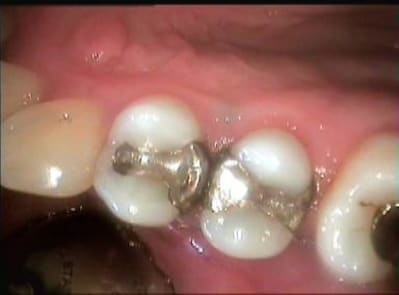

bon ,allons-y: mon très cher marc(exagérons un peu), d'abord il n'y a rien de déshonorant à vendre des BMW et des Mercedes, mais passons, je dirai à mes copains concessionnaires que tu les a mal traités. concernant mon mépris permanent, je t'assure, il fait des pauses, comme tout le monde, il lui arrive même de se mettre en arrêt. alors les inlays: si tu crois que j'ai posé un seul inlay dans ma carrière, là ou une technique directe était indiquée, tu te mets le doigt dans l'oeil. pour des raisons ergonomiques, choisis un doigt de la main droite pour l'oeil droit. je te mets une image d'un inlay posé ce matin sur une 27. sur la 26 l'inlay date de 99. alors si tu crois que c'est une option de luxe, tu n'as rien compris au film. mais je fais aussi des restaurations directes, et comme ben, je prends un plaisir fou à les faire. je te mets également des images, avec digue, tellement compliquée à poser. mais je suis un imbécile: j'aurais du EXTRAIRE ces deux prémolaires et poser deux IMPLANTS, et comme ça, tu peux avoir raison sur toute la ligne. d'ailleurs j'adore poser des inlays et des implants quand ce n'est pas nécessaire, c'est tellement plus fun. quant aux céramo-céramiques, je n'ai JAMAIS poussé à la roue, car, excuse mon excès de modestie, je fais, avec mon céramiste, de très belles CCM aussi. et curieusement, je suis plus serein de façon générale avec les CCM. quant à la tolérance, il y a des maisons pour ça, et non , je ne suis pas tolérant quand un praticien me demande s'il doit acheter un autoclave, je suis intolérant quand un praticien ne PROPOSE pas des implants lorsqu'ils constituent le traitement de choix à long terme, je suis intolérant vis à vis de ceux qui soutiennent sans sourciller, que la digue ne sert à rien. pour le dernier point: nos cabinet sont déjà des entreprises, plus ou moins bien organisées et gérées, dire que l'optimisation de leur gestion et de leur organisation, merci trop peu pour moi, relève de l'autisme et de l'aveuglement. pour conclure, je précise que tout ceci n'est qu'un débat, que je ne connais pas Apap personnellement, et que ça n'a donc rien de personnel.

1 wmsumv - Eugenol

2 tqyljy - Eugenol

001 cnmbk7 - Eugenol

002 bgam24 - Eugenol